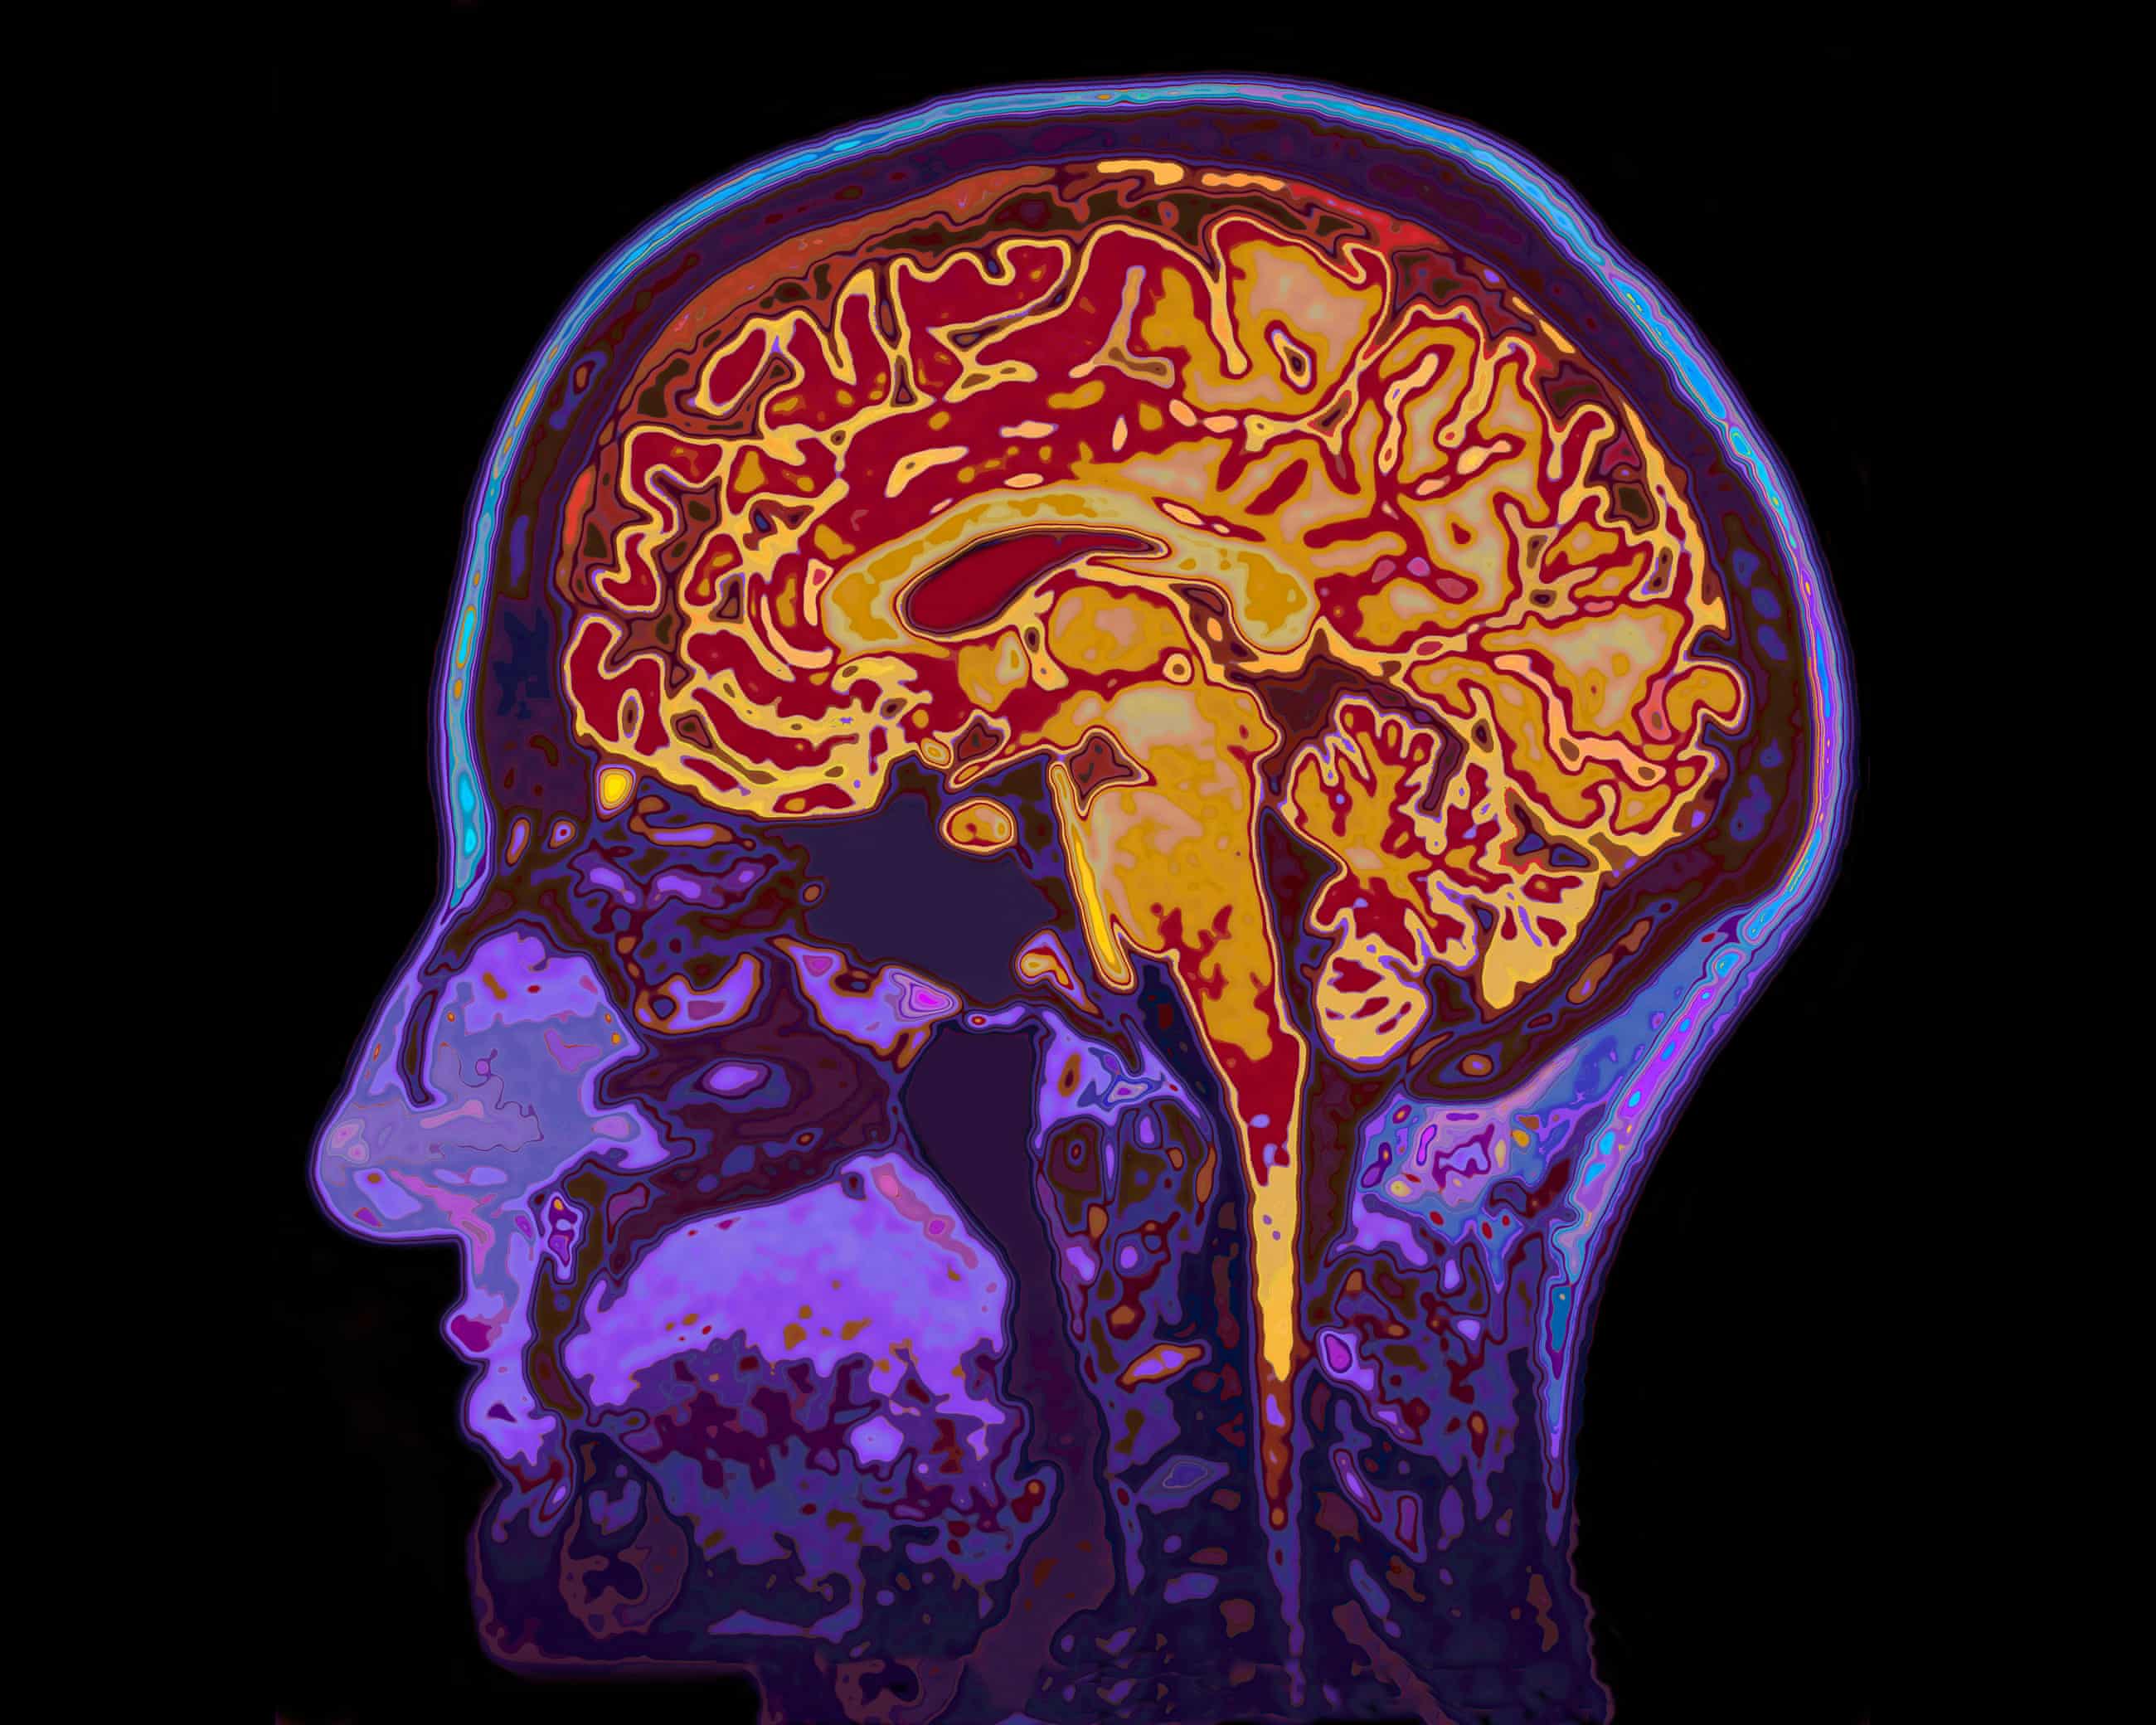

Scans shed light on changes in brain when we zone out while tired

Volunteers took turns to wear an EEG cap while lying in an fMRI scanner for the study. Photograph: Ian Allenden/Alamy